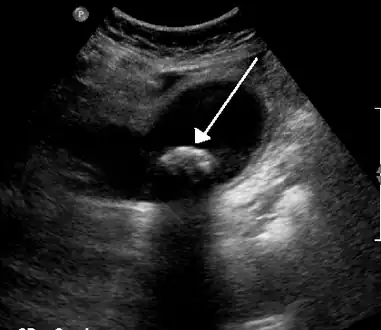

Symptoms can be extremely varied among those suffering from pyruvate kinase deficiency. The majority of those suffering from the disease are detected at birth while some only present symptoms during times of great physiological stress such as pregnancy, or with acute illnesses (viral disorders).[7] Symptoms are limited to or most severe during childhood.[2] Among the symptoms of pyruvate kinase deficiency are:[2]

Gallstones